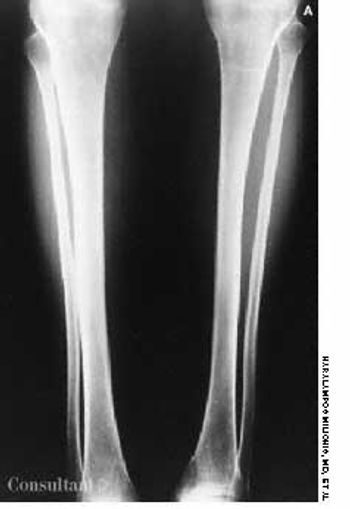

A 33-year-old woman was referred to the endocrinology clinic because of osteoporosis. At age 6, she had fractured her right tibia with no history of trauma; at age 27, she fractured the third lumbar vertebra, and 3 years later she experienced a Colles' fracture of the left wrist. She gave birth to a healthy child 10 years ago.